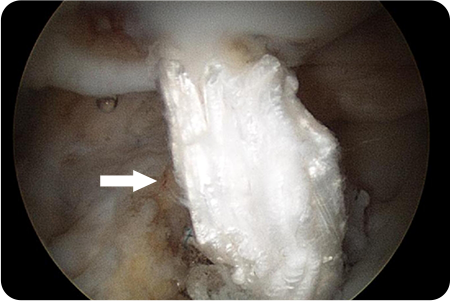

석회제거술

어깨 힘줄 조직에 석회질이 침착하여 발생하게 되는

석회성건염이 있을 때 시행하게 됩니다.

관절경을 이용해 석회주변부에서 염증이 생긴

점액낭을 제거함과 동시에 석회 침착물을 제거

합니다.